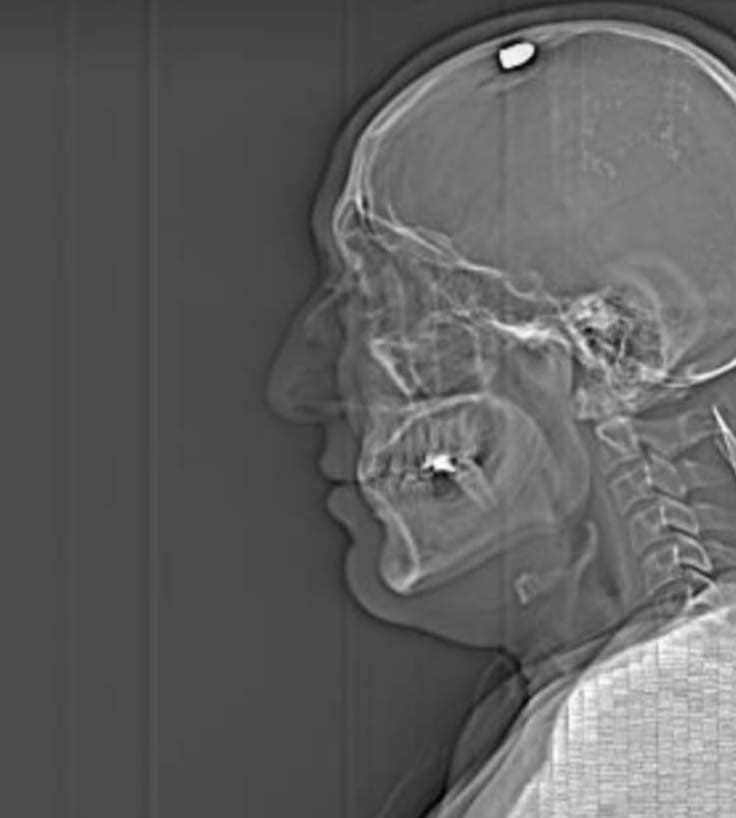

Ölü taklidi yaparak kurtulduğunu söyleyen Koç, “Yere düştüm, bilincim açıktı ama beni tekrar vurmamaları için ölü taklidi yaptım. Orada yaşanan her şeyi duydum. Beni ambulansla hastaneye götürdüler. Kuzenimle onu arayan kişiler daha önce sosyal medyadan tartışmış, birbirlerine hakaret etmiş. Hastanede bir ay tedavi gördüm, ameliyat oldum. Kafatası kemiklerim alındı. İkisinden de şikayetçiyim. Hak etikleri cezayı almalarını istiyorum. Adalete güveniyorum. O an gözümün önünden ailem ve çocuklarım geçti. Çok kötü hissetmiştim” ifadelerini kullandı.